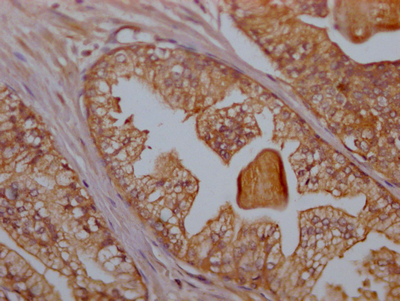

ApplicationELISA, WB, IHC, IF; Recommended dilution: WB:1:500-1:5000, IHC:1:50-1:200, IF:1:20-1:200